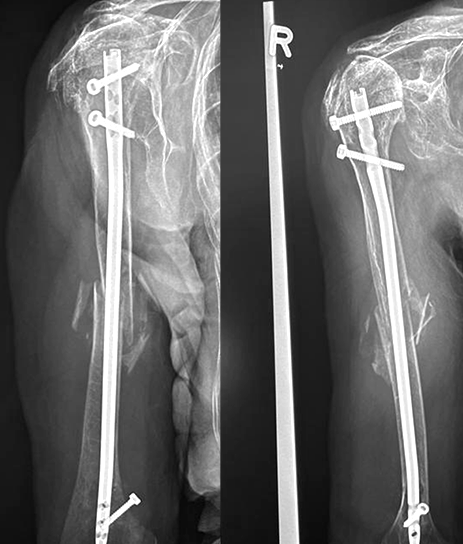

For fracture and revision treatment

The system offers a set of modular Proximal Bodies in several sizes and heights to be paired with a broad range of Modular Stems, available in different diameters and lengths as well as different surface and coating options for cemented and cementless fixation.

The Proximal Bodies’ spiked surface, together with m-l and a-p holes for suture fixation, allow for stable and physiologic tuberosities reattachment. The modular concept of the fracture components supports the surgeon in achieving adequate joint restoration even in cases with poor anatomical landmarks.1